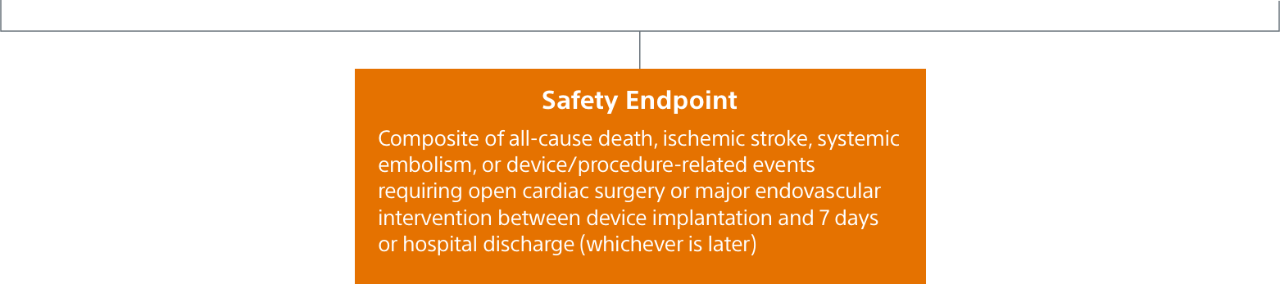

- Primary Safety Endpoint: All-cause death, ischemic stroke, systemic embolism, or device- or procedure-related adverse events requiring surgery or major endovascular intervention within 7 days following the procedure or by hospital discharge, whichever is later.